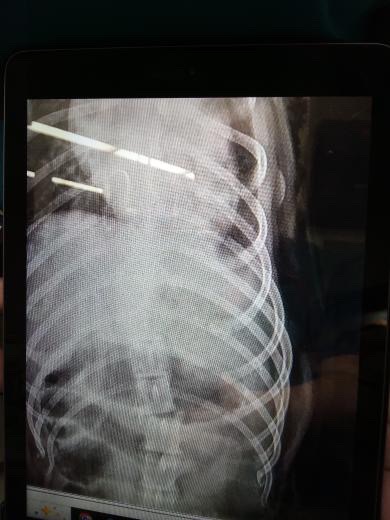

$15,000 is just to raise as much as we can for her surgery. She has a broken back and fractured arms. She needs surgery as soon as possible. She is fighting to live, drinking water, and staying awake. We don’t want to give up on her. Anything that you can give will help, even just kind words and prayers. She helped raise all of us kids and cousins, and we can’t imagine losing her.